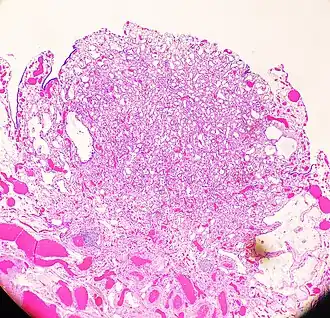

| High-magnification micrograph of an adenomatoid tumor. H&E stain. | |

An adenomatoid tumor of the fallopian tube, low magnification, displaying infiltrative-like borders.

An adenomatoid tumor of the fallopian tube, low magnification, displaying infiltrative-like borders. -

![High magnification of the same case, showing the typical[9] features of tubular spaces of varying size composed of flattened cells resembling endothelium.](./_assets_/Histopathology_of_an_adenomatoid_tumor_of_the_fallopian_tube%252C_intermediate_magnification.jpg) High magnification of the same case, showing the typical[9] features of tubular spaces of varying size composed of flattened cells resembling endothelium.

High magnification of the same case, showing the typical[9] features of tubular spaces of varying size composed of flattened cells resembling endothelium.